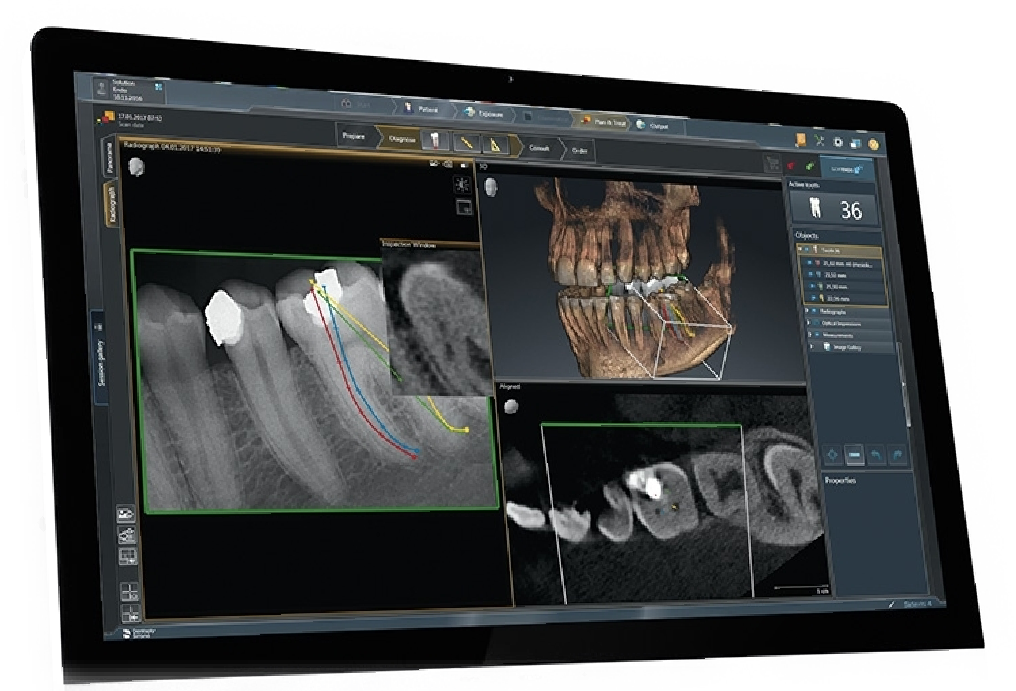

Cone Beam Computed Tomography

Cone beam computed tomography (CBCT) is a radiographic imaging method that allows accurate, three-dimensional (3D) imaging of hard tissue structures. CBCT is the most significant among the medical diagnostic imaging modalities that have emerged recently.

This imaging modality is capable of providing sub-millimeter resolution (2 line pair/mm) images of higher diagnostic quality, with shorter scanning times (~60 s). Radiation exposure dose from CBCT is 10 times less than from conventional CT scans during maxillofacial exposure (68 µSv compared with 600 µSv of conventional CT) and also it has got great dimensional accuracy (only about 2% magnification).

Increasing availability of this technology is now providing the dental clinician an imaging modality, which is capable of providing a 3D representation of the maxillofacial structures with minimal distortion and reduced radiation hazards.

At Dental Scans and Reports we provide full radiological reporting of your scans and also virtual face to face discussion of reports.